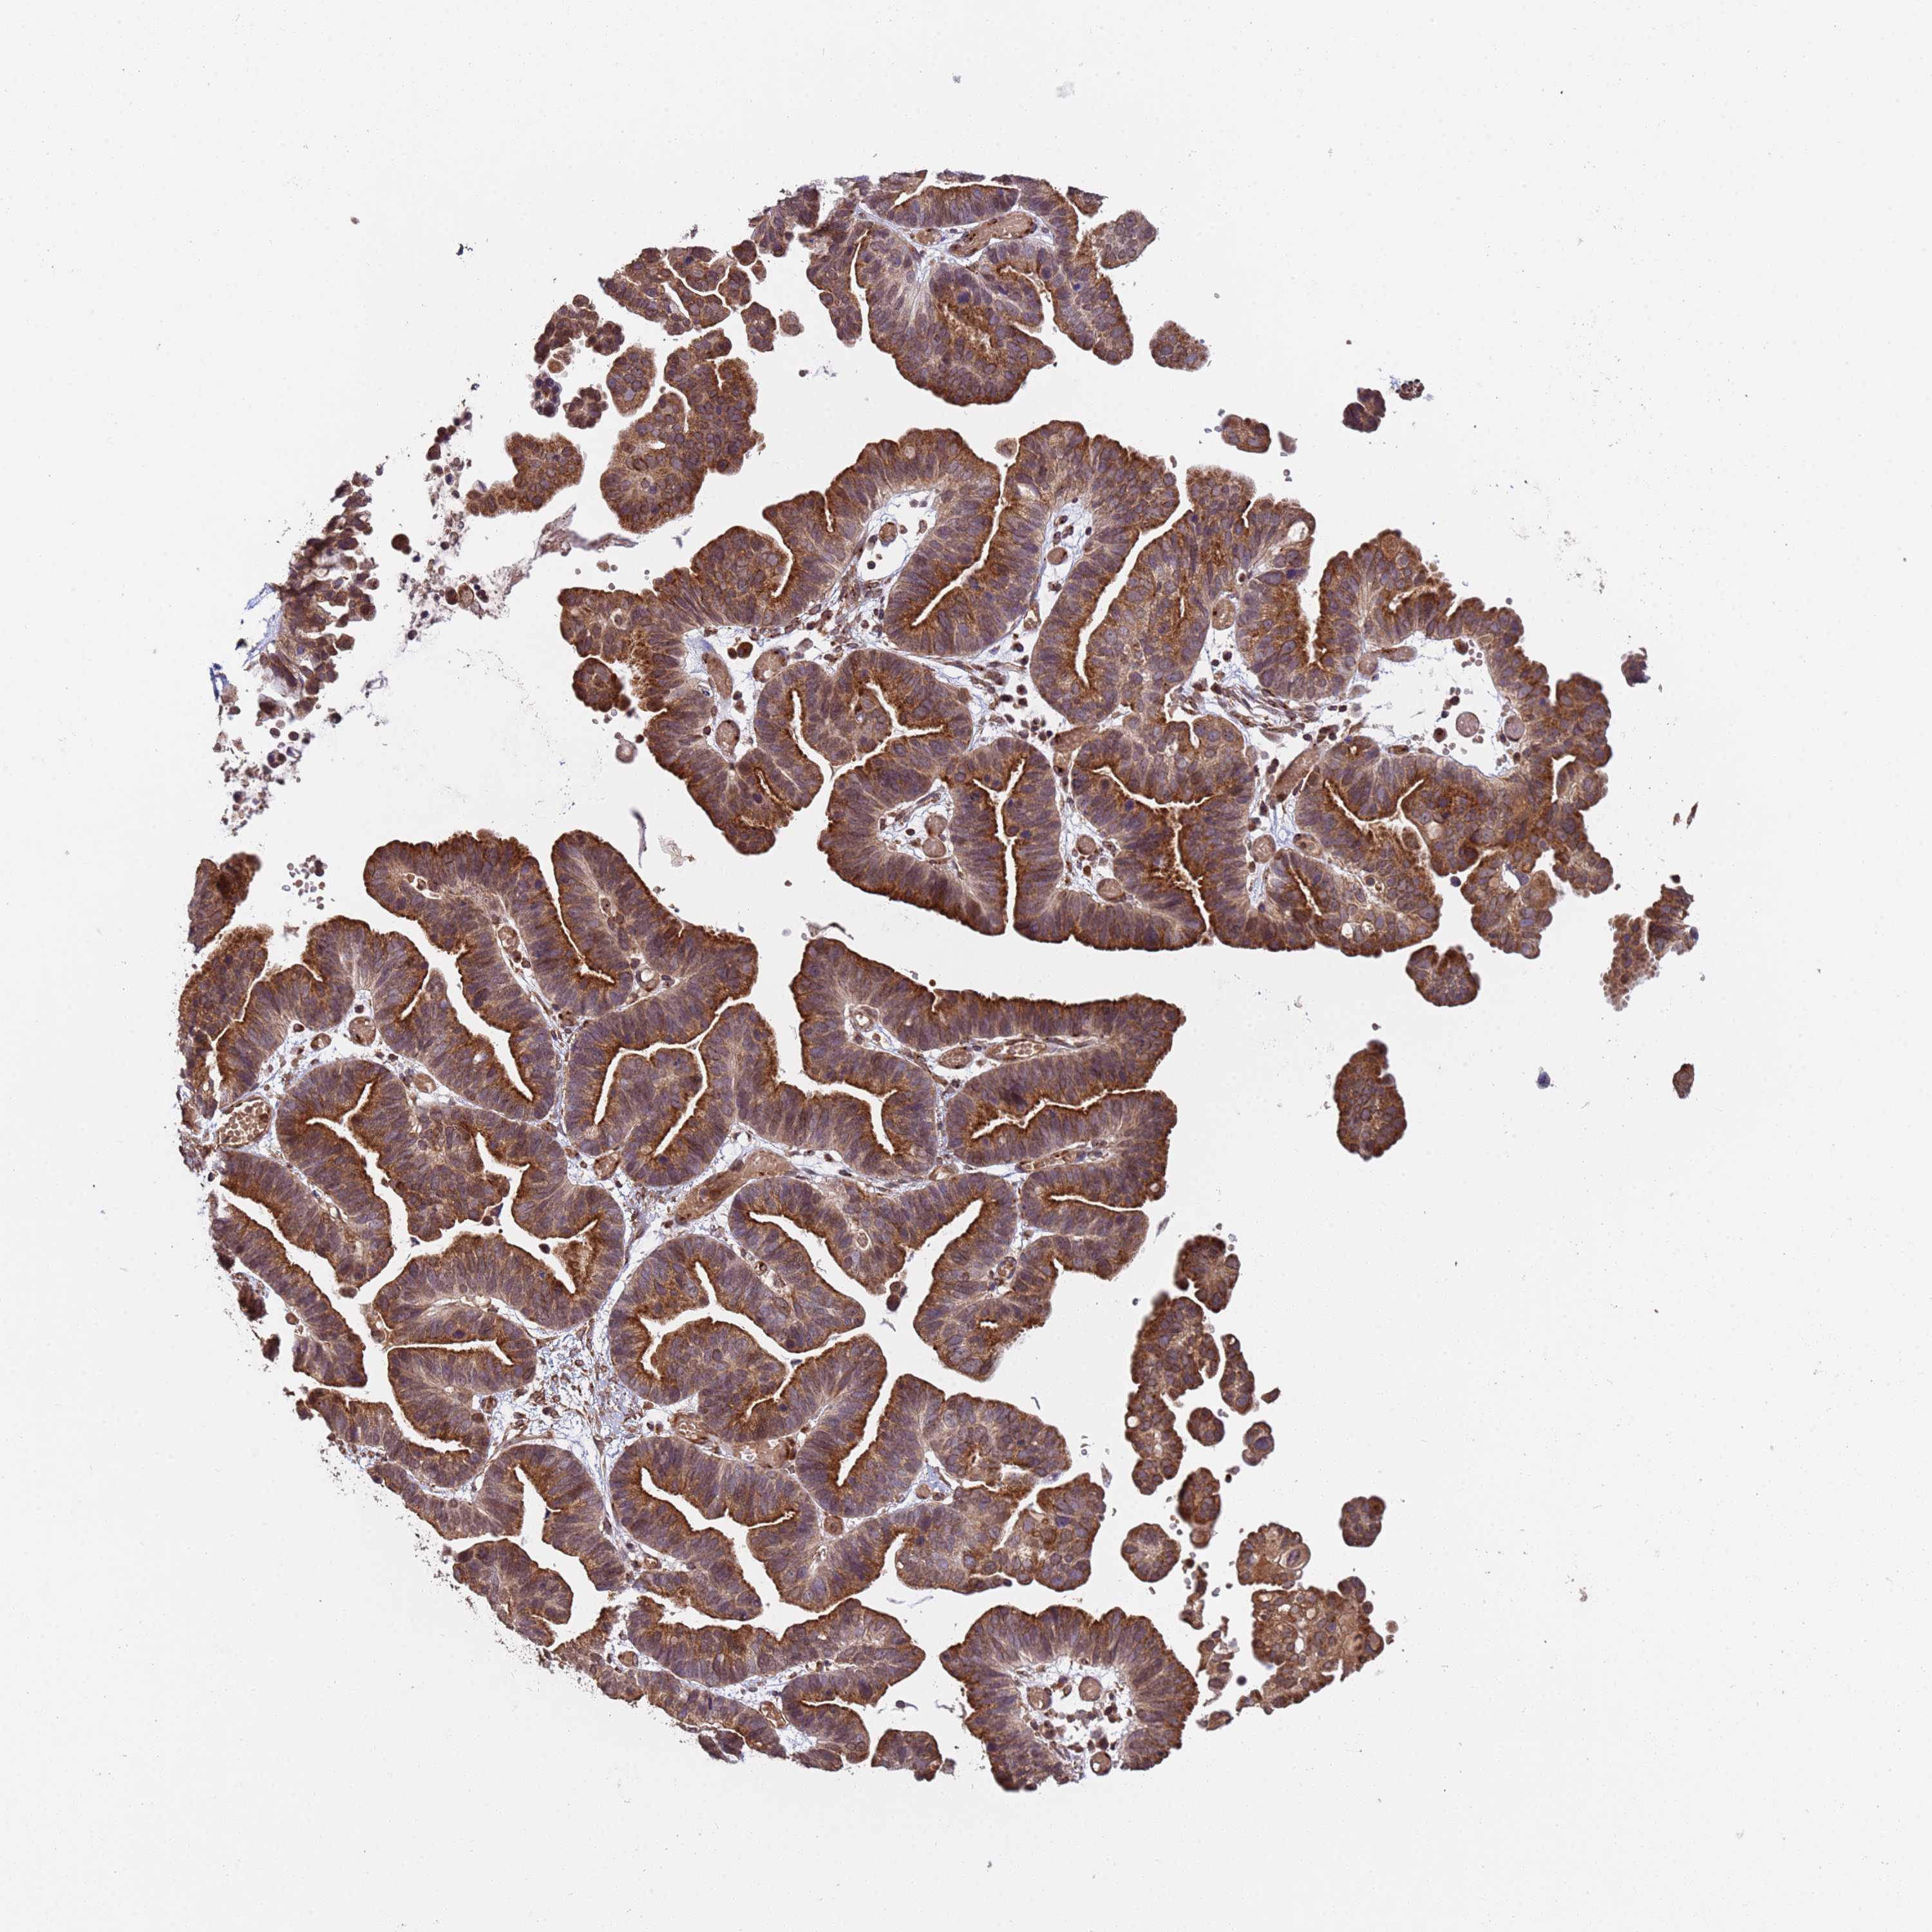

OVARIAN CANCER - Protein expressioni

A mouse-over function shows sample information and annotation data. Click on an image to view it in a full screen mode. Samples can be filtered based on level of antibody staining by selecting one or several of the following categories: high, medium, low and not detected. The assay and annotation is described here.

Note that samples used for immunohistochemistry by the Human Protein Atlas do not correspond to samples in the TCGA dataset.

Antibody stainingi

Antibody staining in the annotated cell types in the current human tissue is reported as not detected, low, medium, or high, based on conventional immunohistochemistry profiling in selected tissues. This score is based on the combination of the staining intensity and fraction of stained cells.

Each image is clickable and will lead to virtual microscopy that enables deeper exploration of all samples and also displays staining intensity scores, fraction scores and subcellular localization as well as patient and tissue information for each sample.

Antibody HPA045624

Staining

High

Medium

Low

Not detected

Intensity

Strong

Moderate

Weak

Negative

Quantity

>75%

75%-25%

<25%

None

Location

Nuclear

Cytoplasmic/membranous

Cytoplasmic/membranous,nuclear

Cystadenocarcinoma, serous, NOS

Carcinoma, endometroid

Cystadenocarcinoma, mucinous, NOS

Carcinoma, NOS